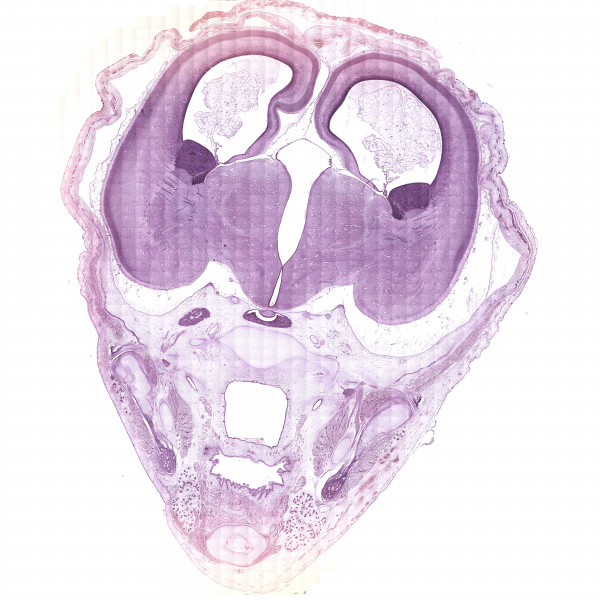

Human brain development atlas

13th gw

H&E